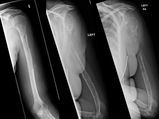

Woman's Bones Vanish Before Doctors' Eyes

Woman's Bones Vanish Before Doctors' Eyes -